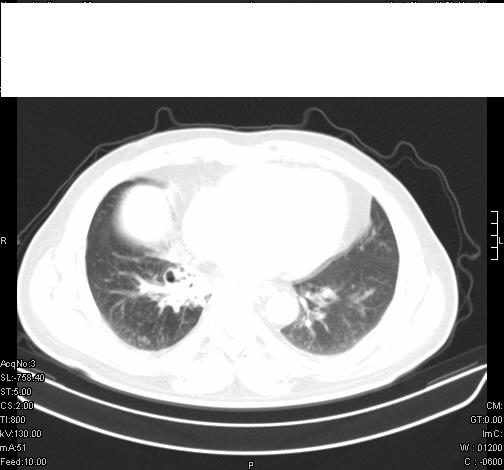

标题: CT6685:右肺阻塞性炎症,增强CT。 [打印本页]

标题: CT6685:右肺阻塞性炎症,增强CT。

前几天,发了患者的平扫片,患者抗炎一周后增强扫描。右中叶病灶吸收明显,但下叶病灶未见明显吸收。右肺门可见结节影,看来凶多吉少

右肺下叶支气管管腔狭窄,管壁增厚,右下肺见斑片状高密度影,考虑右侧肺门中心肺癌伴阻塞性肺炎

右肺下叶散在的斑片状致密影,下叶支气管变窄。考虑:右肺慢性炎症。

第18幅,好像不能简单用炎症解释,前几天我发平扫时,90%人支持肺癌,现在好像大家更倾向于炎症了,我觉得还是不能排除肺癌。

右肺下叶支气管壁明显增厚,考虑癌症并阻塞性炎症、肺门淋巴结肿大

考虑右肺癌并阻塞性炎症、肺门淋巴结肿大

右肺下叶支气管壁不规则增厚,右肺下叶有斑片状影分布。考虑右肺中央型肺癌伴右肺下叶阻塞性改变。建议支纤镜检查。平扫比增强较好显示了病变情况。

右主支气管狭窄,管壁增厚。考虑右中心性肺ca伴阻塞性肺炎。

既然抗炎治疗有效,可继续治疗;右肺下叶支气管管腔狭窄,管壁增厚,右下肺见斑片状高密度影,右侧主支气管后见结节影(淋巴结?),肺癌不能排出。